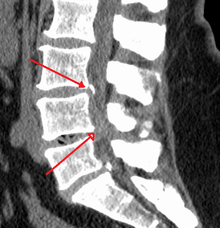

Diagnosis

The diagnosis of spinal stenosis involves a complete evaluation of the spine. The process usually begins with a medical history and physical examination. X-ray and MRI scans are typically used to determine the extent and location of the nerve compression.

CT myelogram

A spinal tap is performed in the low back with dye injected into the spinal fluid. X-Rays are performed followed by a CT scan of the spine to help see narrowing of the spinal canal. This is a very effective study in cases of lateral recess stenosis. It is also necessary for patients in which MRI is contraindicated, such as those with implanted pacemakers.